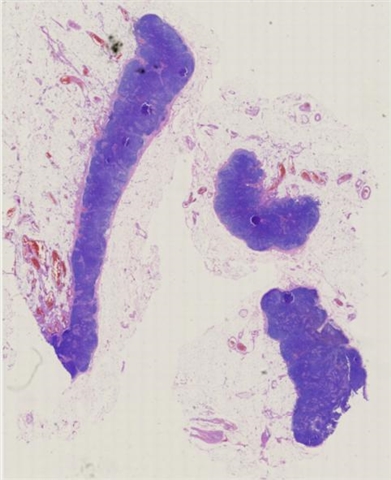

案例3 (7164)

性别:       年龄:19

患者详情: 发现颌下肿块1月,B超检查示颌下腺区域异常低回声,未见淋巴门结构,大小42*23mm,内部见较丰富血流信号,造影均匀等增强,NHL待排。行肿块穿刺活检。全身检查无肿大淋巴结。

大体所见: 巨检:条索状碎组织0.7*0.3*0.1cm。

医院: 复旦大学附属华东医院